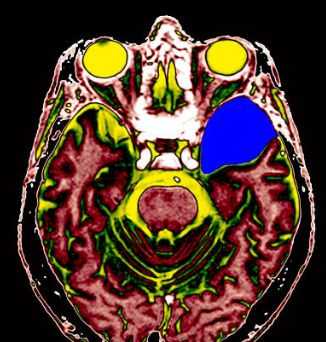

МРТ головного мозга. Т2-взвешенная аксиальная томограмма. Арахноидальная киста. Цветовая обработка изображения.

Арахноидальные кисты представляют собой скопление ликвора между листками расщепленной паутинной оболочки. Арахноидальная киста обычно не сопровождается другими мальформациями. Незначительная часть арахноидальных кист имеет приобретенное происхождение - следствие лептоменингита, операции или кровоизлияния. Частота составляет около 1% от внутричерепных образований. Соотношение полов М:Ж, как 4:1. Типичная локализация - средняя черепная ямка (в области Сильвиевой борозды 50%), межполушарная щель, мосто-мозжечковый угол (11%), за скатом или на уровне четверохолмия (10%), в области червя мозжечка (9%), реже в области межножковой и предмостовой цистерн (3%), а также супраселлярной и хиазмальной цистерн. Ретроцеребеллярная арахноидальная киста довольно часто встречаются за мозжечком и отличима от mega cisterna только по неизменённой задней черепной ямке. Содержимое кисты чисто ликворное, стенки гладкие, чётко очерченные, внутри кисты могут быть перегородки. Мелкие арахноидальные кисты очень трудно увидеть. Меняя ширину окна и его уровень на Т1-взвешенных МРТ изображениях можно заметить, что киста чуть светлее ликвора. Дифференциальная диагностика с эпидермальными кистами лучше осуществляется с помощью МРТ последовательности FLAIR. Эпидермальные кисты становятся яркими, в отличие от гипоинтенсивных арахноидальных.

Арахноидальные кисты представляют собой скопление ликвора между листками расщепленной паутинной оболочки. Арахноидальная киста обычно не сопровождается другими мальформациями. Незначительная часть арахноидальных кист имеет приобретенное происхождение - следствие лептоменингита, операции или кровоизлияния. Частота составляет около 1% от внутричерепных образований. Соотношение полов М:Ж, как 4:1. Типичная локализация - средняя черепная ямка (в области Сильвиевой борозды 50%), межполушарная щель, мосто-мозжечковый угол (11%), за скатом или на уровне четверохолмия (10%), в области червя мозжечка (9%), реже в области межножковой и предмостовой цистерн (3%), а также супраселлярной и хиазмальной цистерн. В зависимости от размера предложено делить кисты на 3 типа (Galassi, 2006), что однако, не имеет практического значения. Ретроцеребеллярная арахноидальная киста довольно часто встречаются за мозжечком и отличима от mega cisterna только по неизменённой задней черепной ямке. При МРТ головного мозга содержимое кисты чисто ликворное, стенки гладкие, чётко очерченные, внутри кисты могут быть перегородки. Мелкие арахноидальные кисты очень трудно увидеть при МРТ головного мозга. Меняя ширину окна и его уровень на Т1-зависимых МРТ изображениях можно заметить, что киста чуть светлее ликвора. Дифференциальная диагностика с эпидермальными кистами лучше осуществляется с помощью МРТ последовательности FLAIR. На них при МРТ головного мозга эпидермальные кисты становятся яркими, в отличие от гипоинтенсивных арахноидальных. Вероятно, вариантом арахноидальной кисты является нейроэпителиальная киста, которая при МРТ головного мозга имеет типичное расположение в области хориоидальной щели.